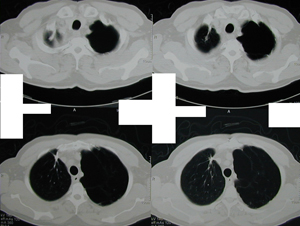

Εικόνα 4

Οπισθιο–πρόσθια ακτινογραφία θώρακος μετά από περιορισμένη θωρακοτομή.

Παρατηρείται πλήρης έκπτυξη του πνεύμονος μετά από αφαίρεση των κύστεων, την αφαίρεση του τοιχωματικού υπεζωκότα και την συρραφή του πνεύμονα στο σημείο της διαφυγής του αέρα.